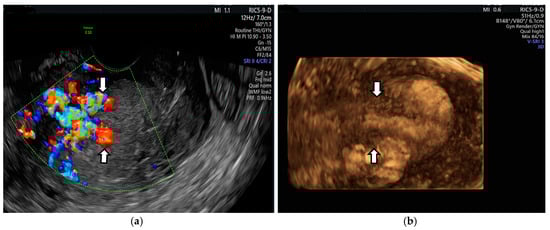

2. Case Presentation